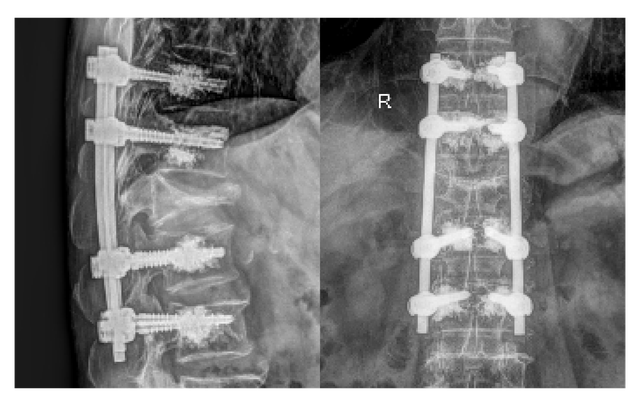

Sau quá trình hội chẩn đa chuyên khoa với khoa Gây mê Hồi sức và khoa Nội Tim mạch, ekip phẫu thuật gồm BS.CKII Lê Trọng Nghĩa và BS.CKI Trương Công Lâm đã thống nhất tiến hành kỹ thuật cố định cột sống bằng vít qua cuống kết hợp bơm xi măng sinh học – một phương pháp điều trị gãy/xẹp đốt sống phù hợp cho người có bệnh nền loãng xương.

Với phương pháp này, ekip tiếp cận vùng tổn thương qua đường mổ phía sau lưng, đặt hệ thống vít chuyên dụng tại các đốt sống T11–T12–L2–L3. Sau đó, xi măng sinh học được bơm tăng cường quanh vít giúp vít bám chắc hơn trong xương loãng, hạn chế nguy cơ lỏng hoặc bung vít. Cuối cùng, các thanh nẹp được lắp để nối hệ thống vít, góp phần cố định cột sống, tái tạo đường cong sinh lý và hỗ trợ chỉnh gù cho người bệnh.

Tái khám sau 15 ngày, tình trạng cột sống của ông T. đã ổn định, người bệnh có thể đi lại sinh hoạt bình thường, không còn tình trạng tê bì chân và đau lưng như trước